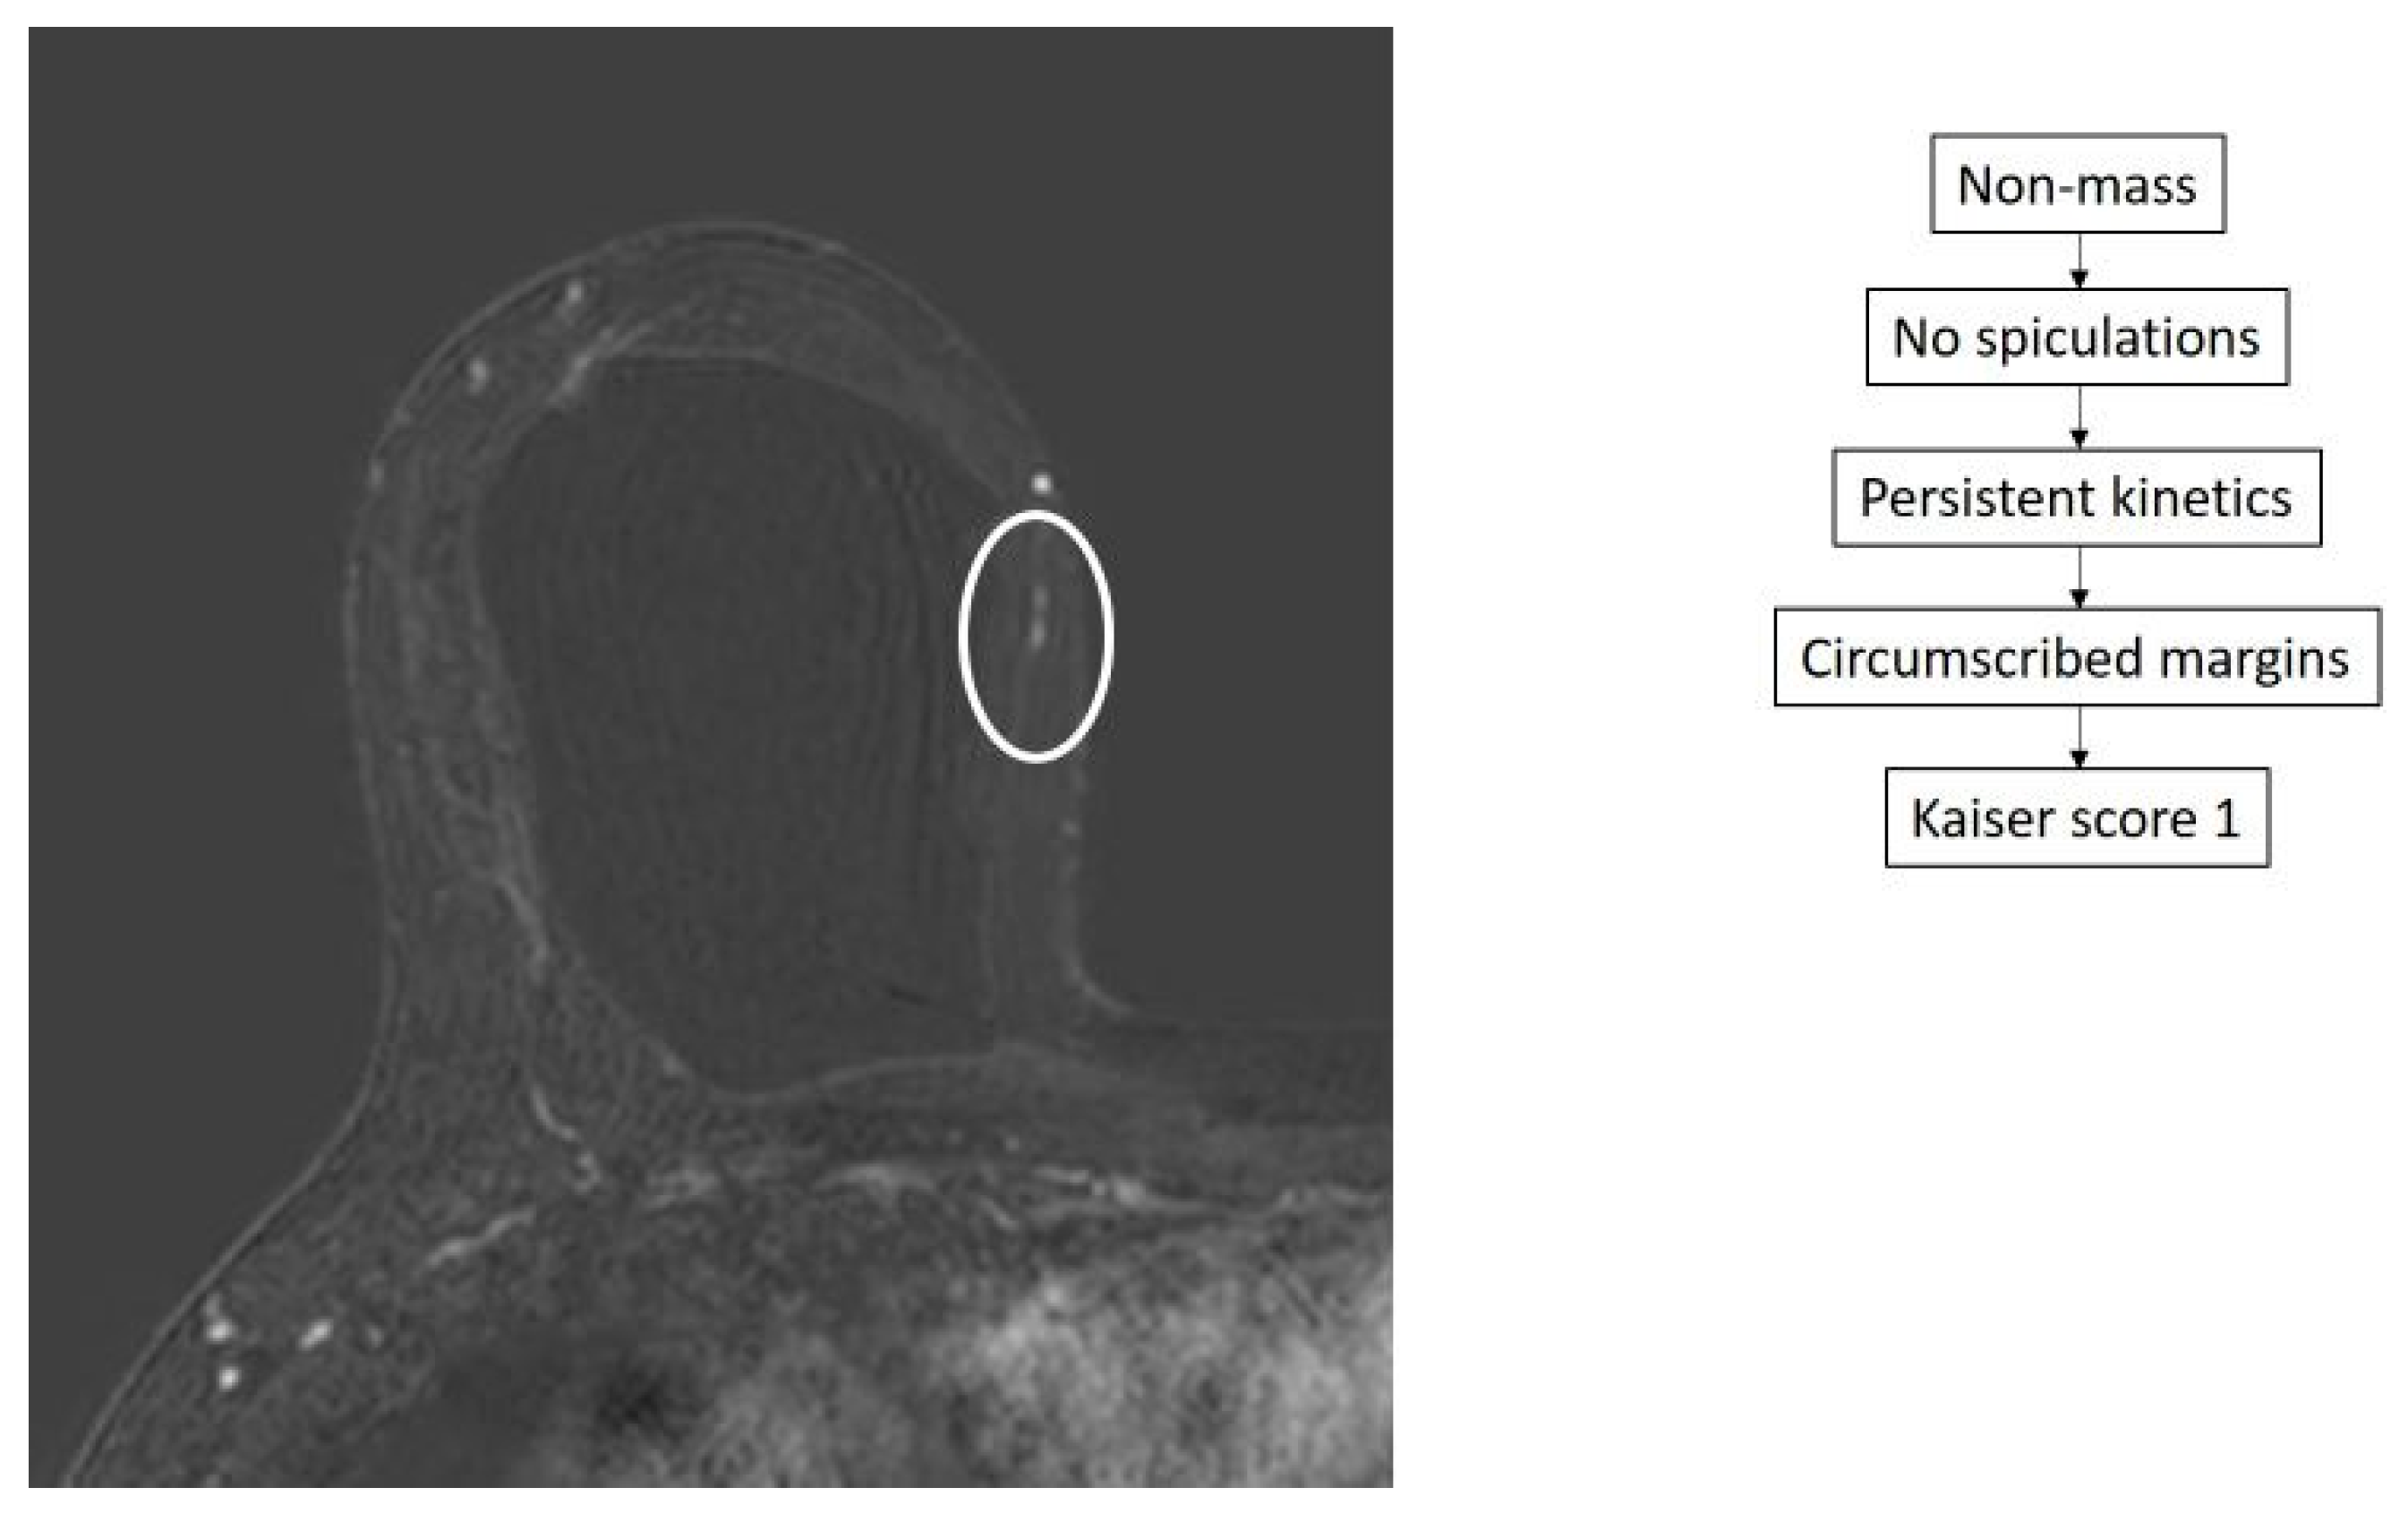

- Dietzel, M.; Baltzer, P.A.T. How to Use the Kaiser Score as a Clinical Decision Rule for Diagnosis in Multiparametric Breast MRI: A Pictorial Essay. Insights Imaging 2018, 9, 325–335. [Google Scholar] [CrossRef] [PubMed]

- Baltzer, P.A.T.; Krug, K.B.; Dietzel, M. Evidence-Based and Structured Diagnosis in Breast MRI Using the Kaiser Score. ROFO. Fortschr. Geb. Rontgenstr. Nuklearmed. 2022, 194, 1216–1228. [Google Scholar] [CrossRef]